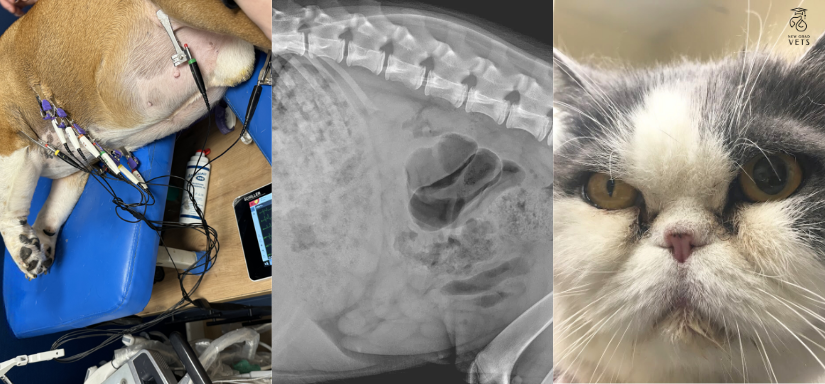

Przez żołądek do serca - czyli nie strać głowy podróżując dookoła świata z newgradvets!

Majówka wypadła w tym roku idealnie - ale po niej dzieje się o wiele więcej i ciekawiej!

Nie ma czasu do stracenia, dlatego już 6 maja startuje kolejna nowość od NEWGRADVETS - kurs Kardiologia Weterynaryjna Część 1 - z lek.wet.spec. Martą Boruczkowską w roli prowadzącej. Absolwentka ESAVS na kierunku Cardiology z sercem na dłoni wprowadzi Cię w świat tego niezwykłego organu, który jeszcze nie raz Cię zaskoczy!

Tydzień później powraca niezastąpiony lek.wet.spec. Przemysław Adach ze swoim kursem Radiologia Jamy Brzusznej - jednym z trzech, które dla Was przygotował i prowadzi! Jako specjalista radiolog i doświadczony chirurg, jak mało kto wie, że liczy się przede wszystkim wnętrze! By zobacz to, czego na co dzień nie widać, nie musisz brać do ręki skalpela - lepiej zacznij od badania RTG, a Przemek pokaże Ci jak zawsze wykonać doskonałe zdjęcie, które opiszesz i zinterpretujesz bez trudu!